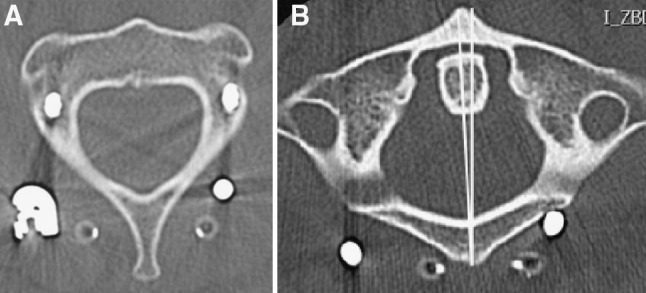

Patient recovered quickly and could be discharged to a rehabilitation clinic. A CT scan showed anatomical reduction with 2° of remaining rotation between C0/1 and C2 (Fig. 5).

Fig. 5.

Postoperative CT scan shows residual C0–C2 rotation of 2°